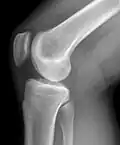

Рентгенограмма коленного сустава в боковой проекции.

Рентгенологическое исследование коленных суставов

Самым доступным, одним из информативных и распространённых исследований является рентгенологическое исследование.

Стандартные проекции, применяемые при рентгенографии коленного сустава — прямая (передне-задняя) и боковая. По мере необходимости их дополняют правой или левой косой, а также аксиальной проекциями. Основным правилом при рентгенологическом исследовании коленного сустава является полипозиционность[2][3].

На рентгенограммах между суставными поверхностями костей видна так называемая рентгеновская суставная щель. Рентгеновской она называется потому, что, будучи заполненной хрящом и прослойкой синовиальной жидкости, которые не дают изображения на рентгенограммах, она имеет вид более прозрачной полосы между суставными поверхностями.

Снимок, выполненный в положении максимального разгибания колена, является стандартным для передне-задней проекции. Он позволяет исследовать переднюю часть суставной щели. Прямой снимок коленного сустава может производиться как в положении лёжа, так и стоя. Когда суставная патология имеет механическую природу и предполагается повреждение связочного аппарата — предпочтительно производить рентгенографию стоя, как при нагрузке, так и в расслабленном состоянии, для исследования суставной щели и оси сустава.

Рентгенологическое исследование коленного сустава в прямой проекции обязательно дополняется боковым снимком. При боковой рентгенографии центральный луч проходит по суставной щели с уклоном на 10° в каудо-краниальном направлении. При этом края мыщелков бедренной кости накладываются друг на друга и их суставные поверхности смещаются в своей задней нижней части. Это позволяет хорошо различать их контуры и оценить состояние бедренно-надколенникового сочленения.